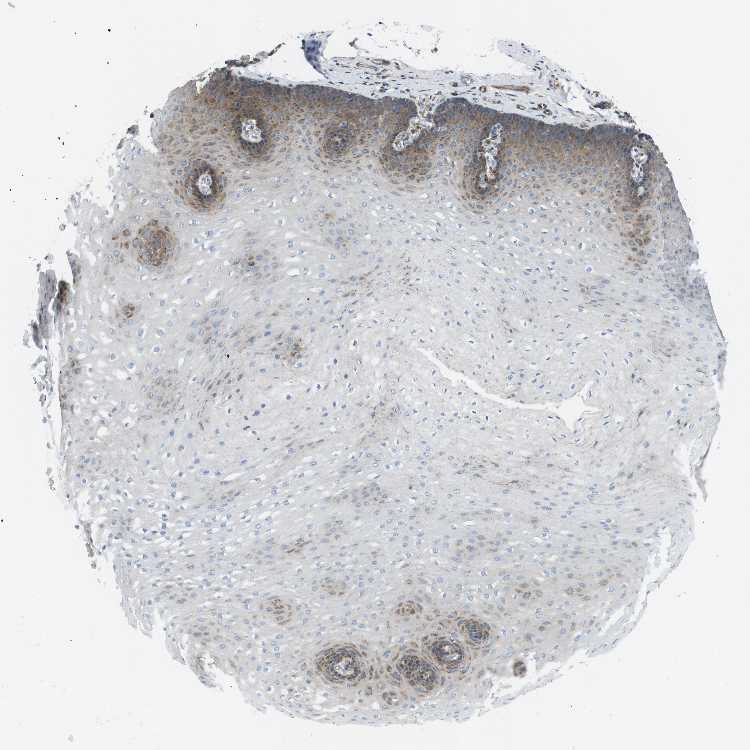

ESOPHAGUS - Antibody stainingi

Antibody staining in the annotated cell types in the current human tissue is reported as not detected, low, medium, or high, based on conventional immunohistochemistry profiling in selected tissues. This score is based on the combination of the staining intensity and fraction of stained cells.

Each image is clickable and will lead to virtual microscopy that enables deeper exploration of all samples and also displays staining intensity scores, fraction scores and subcellular localization as well as patient and tissue information for each sample.

Antibody HPA014711Antibody HPA070816

Squamous epithelial cells LowNot detected